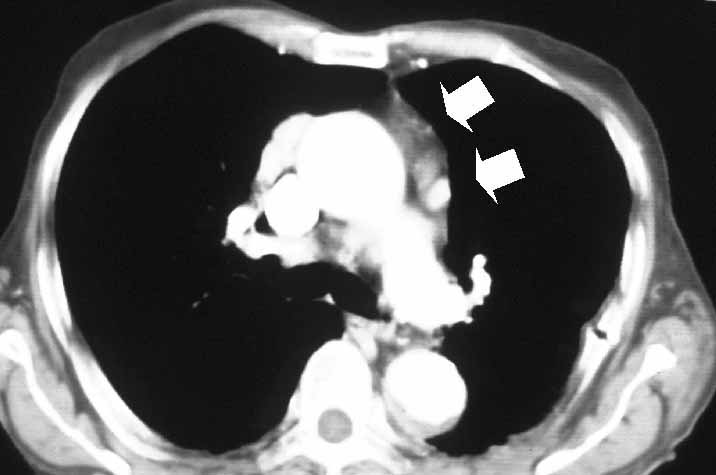

View image largerFigure 12. Computed tomography of the chest showing residual thymic tissue following previous unsuccessful transcervical thymectomy.

VATS thymectomy can also be employed to reoperate on patients with refractory MG who already underwent unsuccessful transcervical or sternal splitting thymectomy (Figure 12). This particular indication must still be considered investigational; however, it is worthy to note that in a series of 8 patients, we found at reoperation residual thymic tissue in all patients and 6 patients achieved sustained symptomatic improvement.